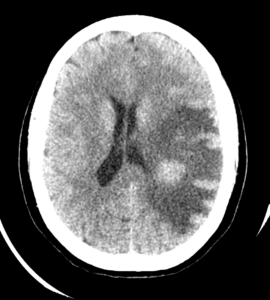

HALLAZGOS RADIOLÓGICOS